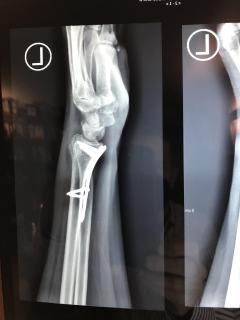

Υπάρχουν διάφορες χειρουργικές τεχνικές και υλικά που χρησιμοποιούνται, ανάλογα με τη μορφολογία του κατάγματος. Μετεγχειρητικώς ενδέχεται να εφαρμοστεί ολιγοήμερη ακινητοποίηση. Εαν απαιτηθεί φυσιοθεραπεία, αυτή είναι καλό να γίνεται μετά την 6η μετεγχειρητική εβδομάδα.

Περίπτωση 2ου ασθενούς